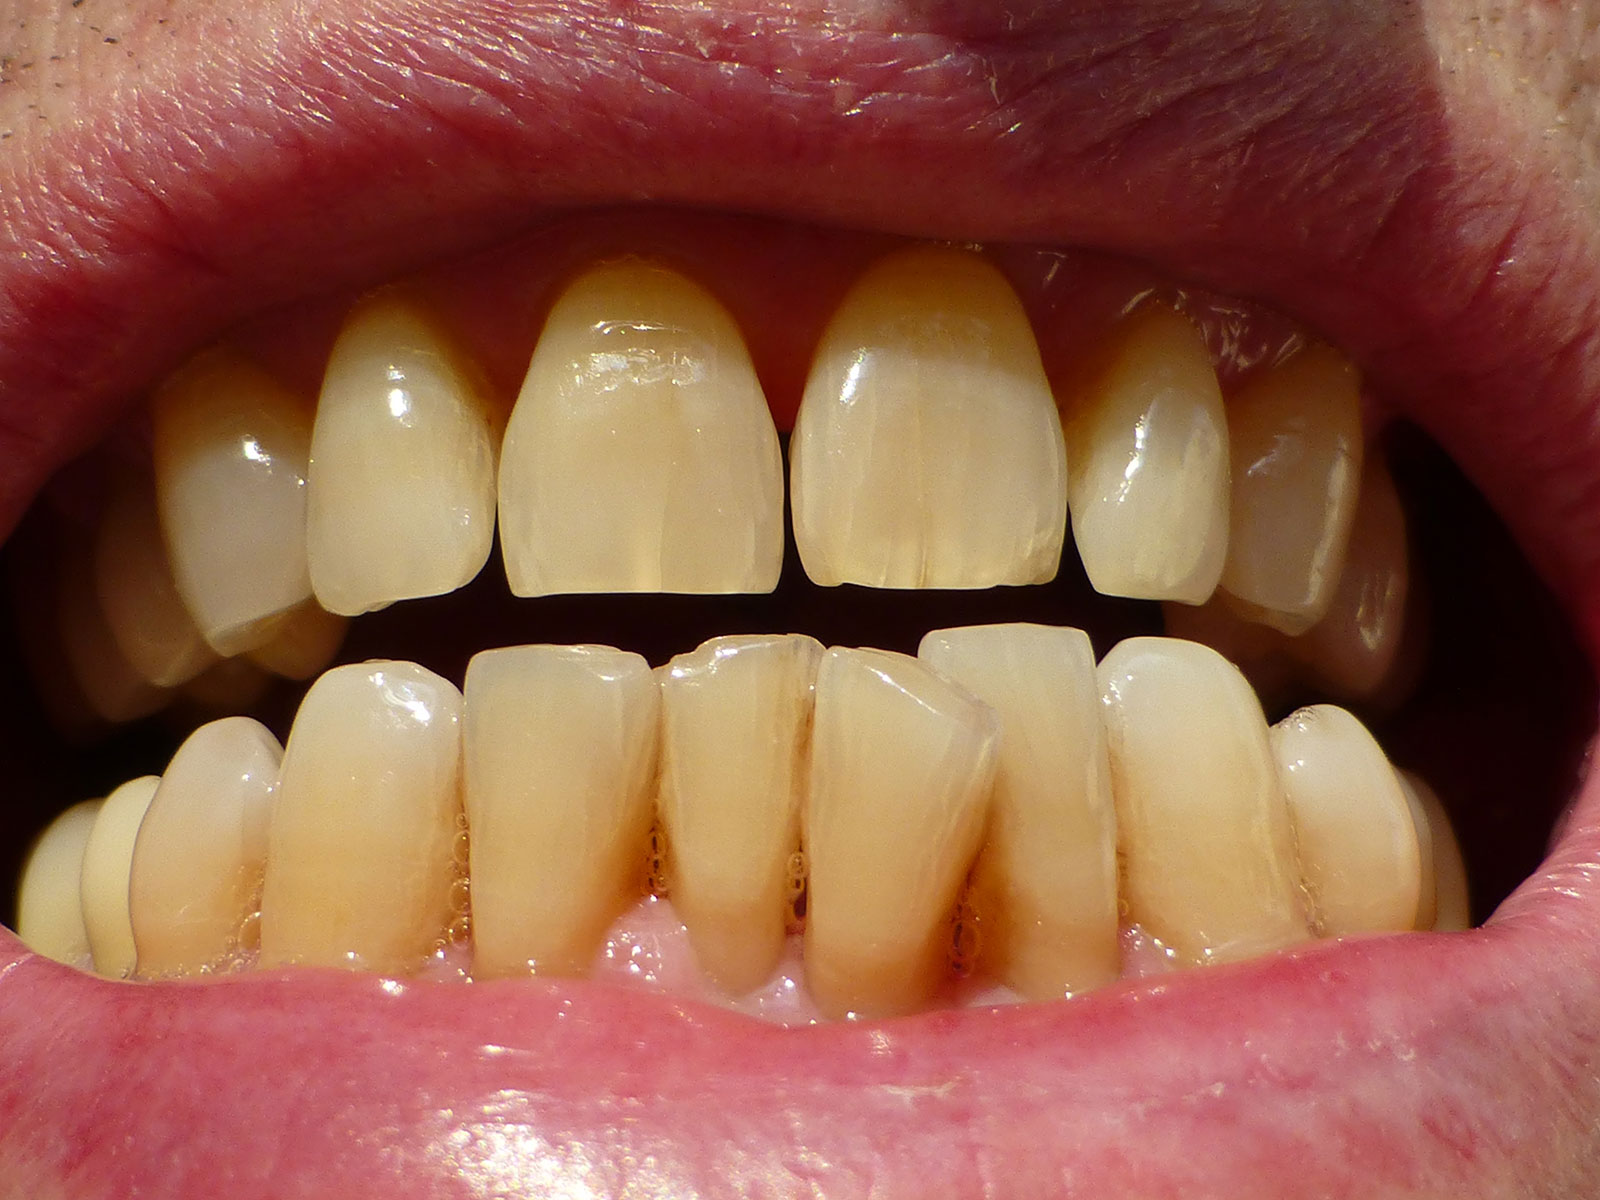

Orthognathic surgery involves the surgical manipulation to correct a wide range of minor problems with the jaw and facial structure caused by growth, sleep apnea, TMJ disorders, imperfect positioning of the teeth or other orthodontic problems that cannot be fixed with braces. Surgery can help improve a person’s speaking, chewing and breathing.